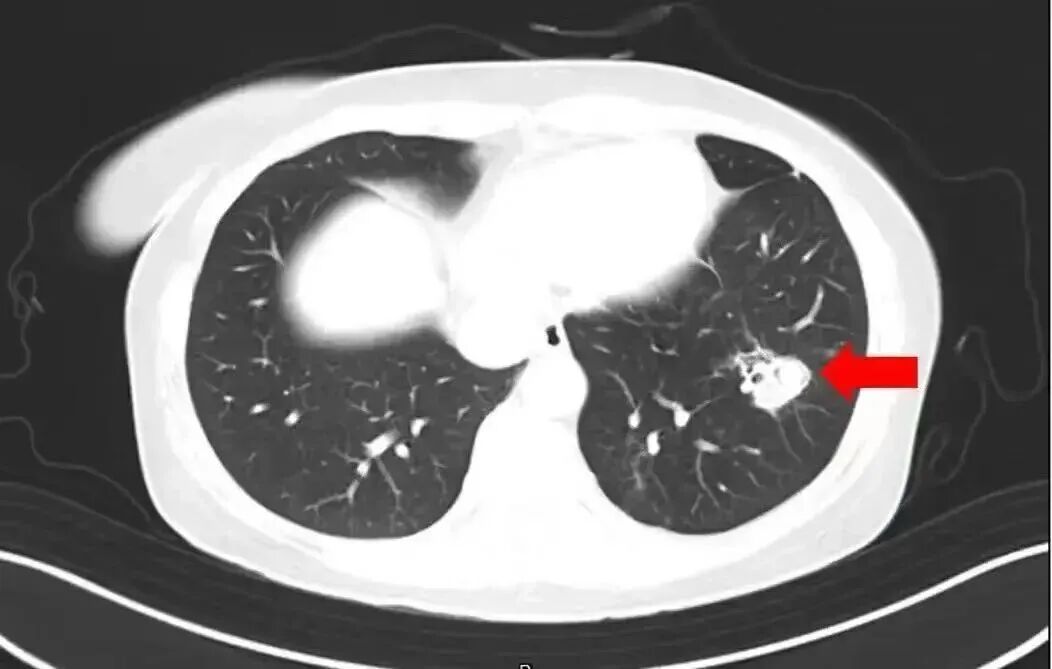

近日,一6岁女童因持续发烧17天且意识不清,被转至郑州郑大一附院治疗。医生检查后大吃一惊:孩子脑子竟被“啃”出大大小小十几个洞,再晚来几天可能会被“啃空”。抽取洞内积液检测后,医生锁定了“真凶”——烟曲霉菌。

医生介绍,烟曲霉菌常隐藏在潮湿环境中,孩子在此玩耍后,霉菌通过呼吸道进入血液系统,进而“爬”进了脑子。

2025年1月,江苏扬州的张大爷为迎接春节开始大扫除,清扫过程中不慎吸入大量灰尘和霉菌孢子,导致哮喘发作。张大爷随即服用了常备的哮喘治疗药物,可症状反而逐渐加重。经检查,张大爷的肺部出现感染,确诊为肺曲霉病。